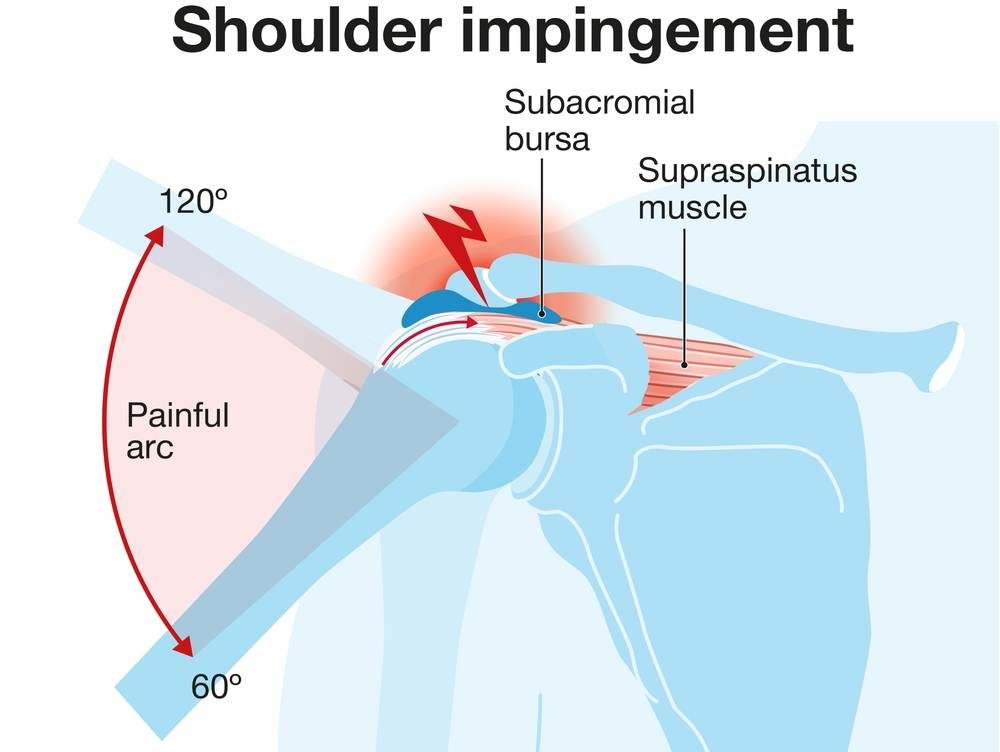

Shoulder Impingement

Pain caused by tendon compression during movement.